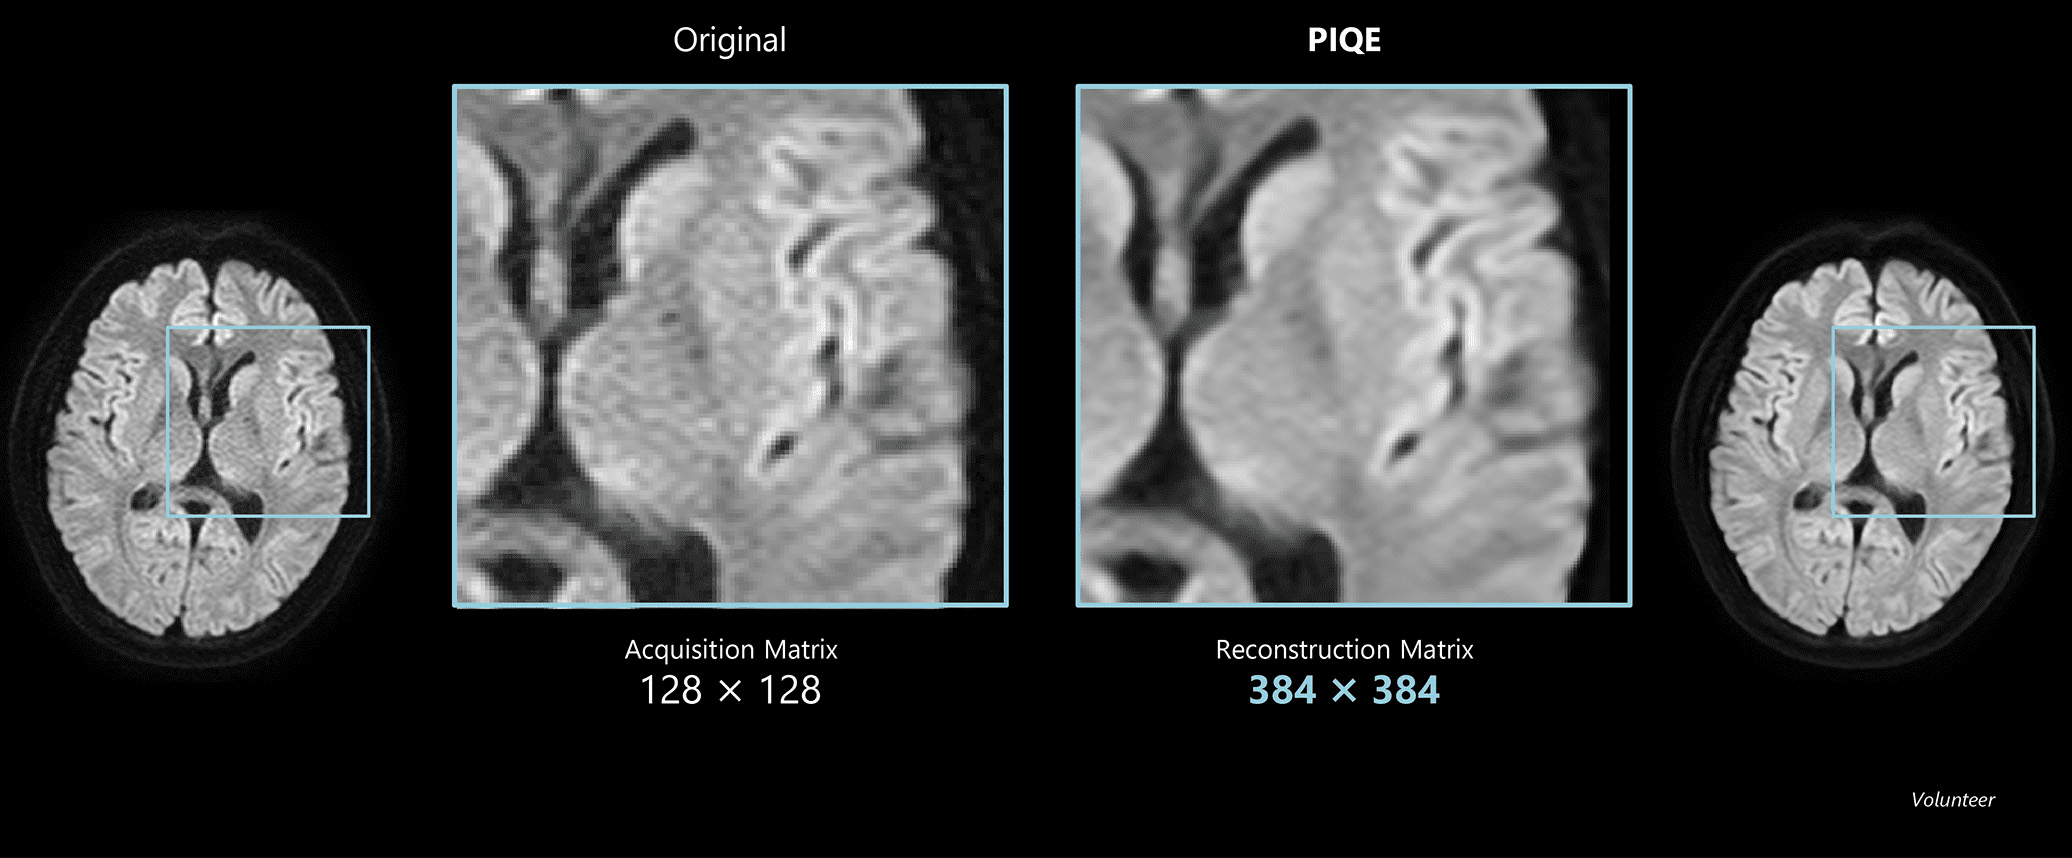

Volunteer image with PIQE adapted to SEEPI DWI sequence.

Structural detail can be more finely captured at three times the resolution with PIQE.